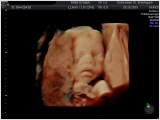

d.h. pränataler Ultraschall (Messung der Nackendicke, Organscreening) einerseits, andererseits kann noch eine Untersuchung mittels 4D-Ultraschall durchgeführt werden,

wo ein dreidimensionales Bild von Ihrem Kind angefertigt werden kann.

Dieses ermöglicht die Diagnostik einiger Fehlbildungen wie etwa der Lippen-Kiefer-Gaumenspalte, andererseits kann so das erste "Foto" von Ihrem noch ungeborenen Kind gemacht werden, was die Mutter-Kind-Beziehung zusätzlich fördert.